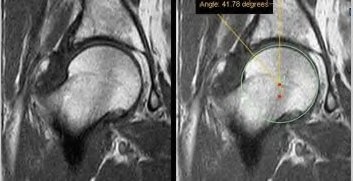

A 75-year-old man underwent total hip arthroplasty 10 years ago. He now reports mild groin pain which has been increasing lately. What is the most likely explanation for the finding in Figure A indicated with the arrows?

Osteolysis of the pelvis is a common complication associated with total hip arthroplasty. Osteolysis affects sockets with and without cement, and has been attributed to the biologic reaction to wear debris. With well-fixed cementless sockets, an expansile pattern of osteolysis is usually seen.

The radiographic appearance has a radiolucent area that starts at the implant-bone interface and expands into the cancellous bone away from the implant.

This pattern of osteolysis can be explained with the concept of effective joint space. This concept states that joint fluid and wear particles will flow according to pressure gradients and follow the path of least resistance.

The Level 5 review article by Chiang discusses osteolysis in further depth.